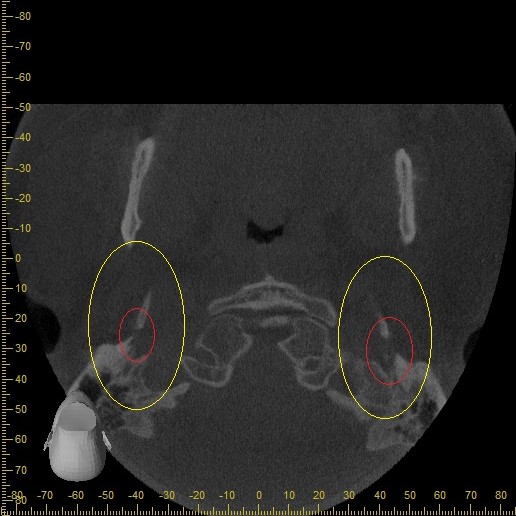

Below are some screenshots from my Cone Beam CT scan and the report linking possible ES. I have more Regular CT scans I could possibly share and/or if you would like me to get possible better angles from the Cone Beam CT scan let me know. But as of right now I’m at a loss as what to do going forward. I do have an MRI with and without contrast of the Cervical Spine Scheduled, but that’s due to the doctor’s (the doctor that dismissed it as ES and one doctor that wants to follow up and learn more on it) wanting it.

- Now onto this year, I finally got better back to full health in late November early December 2024 and sadly started to get another sinus infect in January and still no answers to why. I just happen to be watching YouTube when a Dentist had said that your teeth could be linked to sinus issues causing sinus infections and normally the only way to tell if this is the case is to get a Cone Beam CT scan. I then thought this could be another lead to find out why I keep getting sick as I did when I was 10 have my first top premolar on my left side removed against what I wanted as they said my teeth were too crowded and it needed to be removed so I could have braces (which that dentist didn’t even do my braces anyway). But I thought when he removed it if a small piece of the root was still in there as he just broke out the tooth without removing it via surgical means that that could cause an abscess in my Left Maxillary Sinus where infections always start. So, finally I was able to find a place that would give me a Cone Beam CT scan back in February of this year all while I was just starting to get sick from my infection. Anyway, I finally got the report in March and found out oddly my Left side is mostly normal other than mucus polyps, but I have a few other issues (I have attached the report below). This report is where I first found out about Eagle Syndrome as it states I might have Calcified Ligaments and further testing is needed to confirm. It was only after this report and looking up what Eagle Syndrome was that I can say I have almost every symptom that has ever been reported. Sadly, I couldn’t find anyone in my State at the time that work with Eagle Syndrome and when I did was about a week before I found this site and the doctor I did see seemed to dismiss me as another hypochondriac and you can’t have it as you don’t have Vertigo type Dizziness, my styloid are normal length and I don’t have neck pain equivalent to having to be in a neck brace. Not only this she only looked at my CT scan from a week earlier that I had got in Emergency. The Emergency visit was due to the fact at 8PM that night I had pain in my Right Mastoid Bone, and I was starting to get an earache. I went to lay down and took pain meds and an ice pack in hopes to reduce the pain and swelling. I couldn’t sleep due to the pain and came upfront about 10PM. 10:21PM I couldn’t take it anymore and started to stretch my neck and I felt a huge snap and heard a load pop, all the pain just felt like it disappeared. One minute later, I had a massive pain that spread just like when you get an IV that stings, but it felt like someone was trying to murder me and stabbed a knife into the right side of my skull. I was in so much pain that I was hunched over, and we had to have an ambulance called. I thought I was having an aneurism and my mother thought I was having a Stroke (very rare ES Symptom). When the ambulance arrived, they took my vitals, and my blood pressure was 148/110 with a pulse in the high 90’s low 100’s. Luckily the pain had subsided enough that we were able to go to emergency without the ambulance ride, but while I was in emergency the pain had spread to my left side of my head and now felt like someone had taken a clothes iron and stuck it on my head. Any breeze moving my hair was pure agony and I couldn’t lay my head on a pillow without that burning pain. According to emergency though I must have just had a Mastoid Process infection and it burst. Luckily the pain went away by the time I went to the Doctor for ES, but like I said before they were of no help.